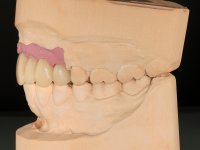

The diagnostic wax-up enclose the possibility to include, or not, gum-shade ceramics to rehabilitate the interdental papillae. This two possibilities were presented to the patient due to the bone regeneration unpredictability (in our opinion), mainly vertically.

The wax-up allowed us to do a mock-up that worked also as a radiological template. The CT-scan was imported to an implant planning software where three dental implants were simulated, and a surgical guide developed.

10 weeks after the surgery, a first impression was done to do a CAD-CAM provisional bridge (based on the diagnostic wax-up), that worked the soft tissue architecture during two months. This architecture was copied in a second impression by individualizing the impression copings in their emerging profile.

The working model was scanned and the dental technician developed a zirconia framework based on the diagnostic wax-up. This framework try-in was done, the perfect fit was assessed, and a final impression was done with a light silicone.